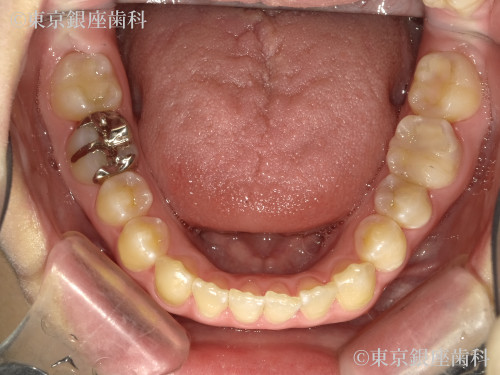

Before

疾患 矯正

施術内容 矯正

インビザライン:コンプリヘンシブパッケージ